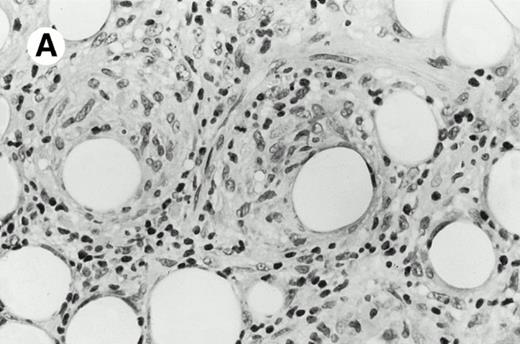

Three cases (cases no. 1 to 3) were located in the nasal cavity. The neoplastic infiltrate consisted of medium and/or large pleomorphic lymphoid cells (Fig 1)intermingled with variable numbers of small lymphoid cells, plasma cells, eosinophils, and histiocytes. Features of angiocentrism and angioinvasion, epitheliotropism, and areas of necrosis were observed in all three cases. Patient no. 4 presented with disease restricted to the lung and an open-lung biopsy was available. The neoplastic infiltrate was composed of large atypical lymphoid cells and was predominantly interstitial without extensive destruction of the normal architecture. Features of angiocentrism, angioinvasion, and epitheliotropism were present (Fig 2A and B). Case no. 5 involved the larynx, extending to the piriform sinus, the ventricle, and the arytenoid. One month later, the lymphoma disseminated to the subcutaneous tissue in the spinal region and biopsy specimens from both sites were available. The neoplastic cells were medium and large, with abundant clear cytoplasm and slightly irregular nuclei with dense chromatin. Epitheliotropism was present in the larynx mucosa. Small foci of necrosis and angiocentrism were seen without angioinvasion. Three patients presented with cutaneous disease. Cases no. 6 and 7 were comparable, as both histories started with necrotic subcutaneous nodules of the thigh, which on histologic analysis were characteristic of cytophagic histiocytic panniculitis without evidence of lymphoma (Fig 3A). Second excisional biopsies of cutaneous nodules obtained 7 and 5 months later, respectively, showed characteristic features of lymphoma in both cases (Fig 3B). However, in case no. 6, skin biopsy specimens showed an epidermotropic PML lymphoma extending to the dermis and the subcutaneous tissue, whereas in case no. 7, the neoplastic infiltrate consisted of a PSC confined to the subcutaneous tissue, admixed with benign histiocytes that showed phagocytosis. Patient no. 8 presented with recurrent skin lesions with spontaneous remission over a period of 10 years. The initial skin biopsies demonstrated an intense epidermotropic neoplastic infiltrate that extended to the superficial and deep dermis composed of atypical PML cells. All cutaneous cases displayed features of angiocentrism, but angioinvasion was observed only in case no. 6 and foci of necrosis in cases no. 6 and 8.

Subcutaneous γδ T-cell lymphoma (case no. 6). (A) Initial biopsy sample shows characteristic features of cytophagic histiocytic panniculitis without evidence of lymphoma cells; (B) second biopsy performed 7 months later demonstrates involvement of the subcutaneous tissue by a pleomorphic γδ T-cell lymphoma (hematoxylin-eosin stain).